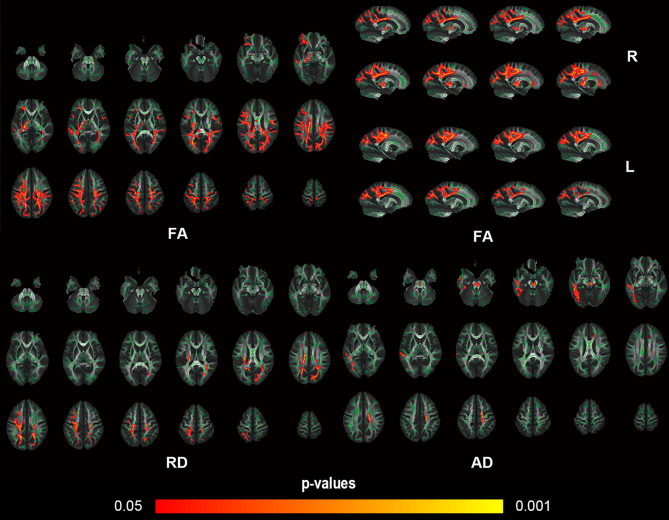

Methods: Forty-two type 2 and 3 pediatric SMA patients and 42 age- and gender-matched healthy controls (HC) were prospectively enrolled in this study. The tract-based spatial statistics (TBSS) was used to assess white matter integrity and the structural network properties were calculated based on DTI white matter fiber tracking and the graph theory approach. A partial correlation was performed to explore the relationship between white matter parameters and clinical characteristics.

Results: In total, 42 patients (mean age, 10.86 ± 4.07 years; 23 men) were included. TBSS analysis revealed widespread white matter changes in SMA patients. The SMA patients showed changes in multiple small-world and network efficiency parameters. Compared to the HC group, SMA showed increased characteristic path length (Lp), normalized clustering coefficient (γ), small-world characteristic (σ), and decreased global efficiency (Eglob) (all p < 0.05). In the node properties, right supramarginal gyrus, right orbital part of superior frontal gyrus, right supplementary motor area, and left median cingulate and paracingulate gyri changed in SMA patients. A decreased axial diffusivity (AD) value was associated with lower Hammersmith Functional Motor Scale-Expanded scores (r = 0.45, p = 0.02), which means that the symptoms of SMA patients are more severe.